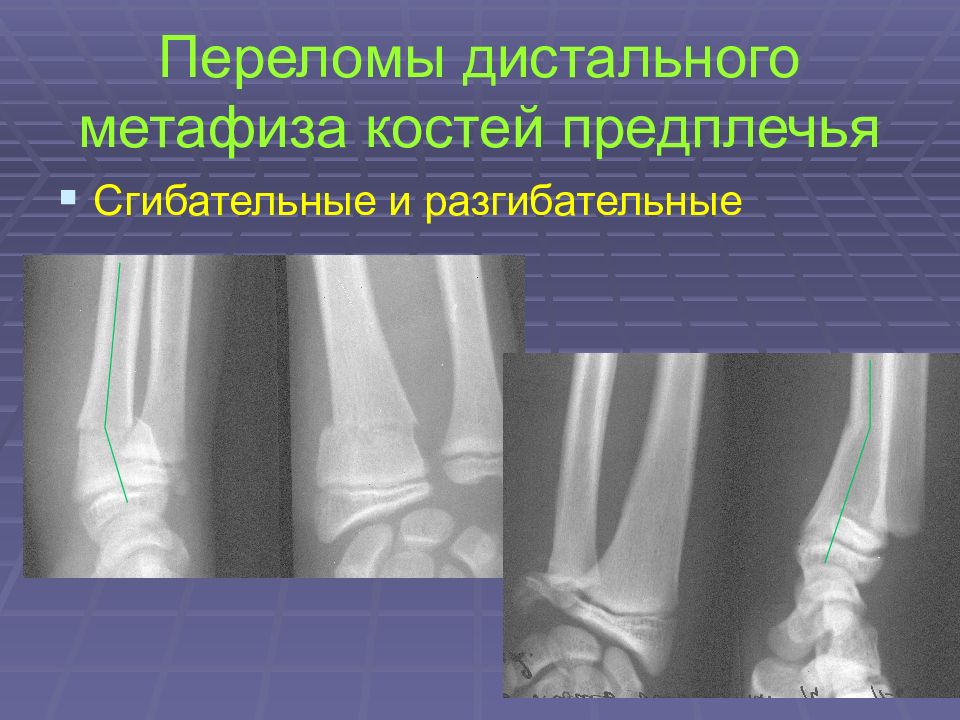

Слайд 35: Переломы дистального метафиза костей предплечья

Слайд 36: Переломы дистального метафиза костей предплечья

Сгибательные и разгибательные

Слайд 37: Переломы дистального метафиза костей предплечья